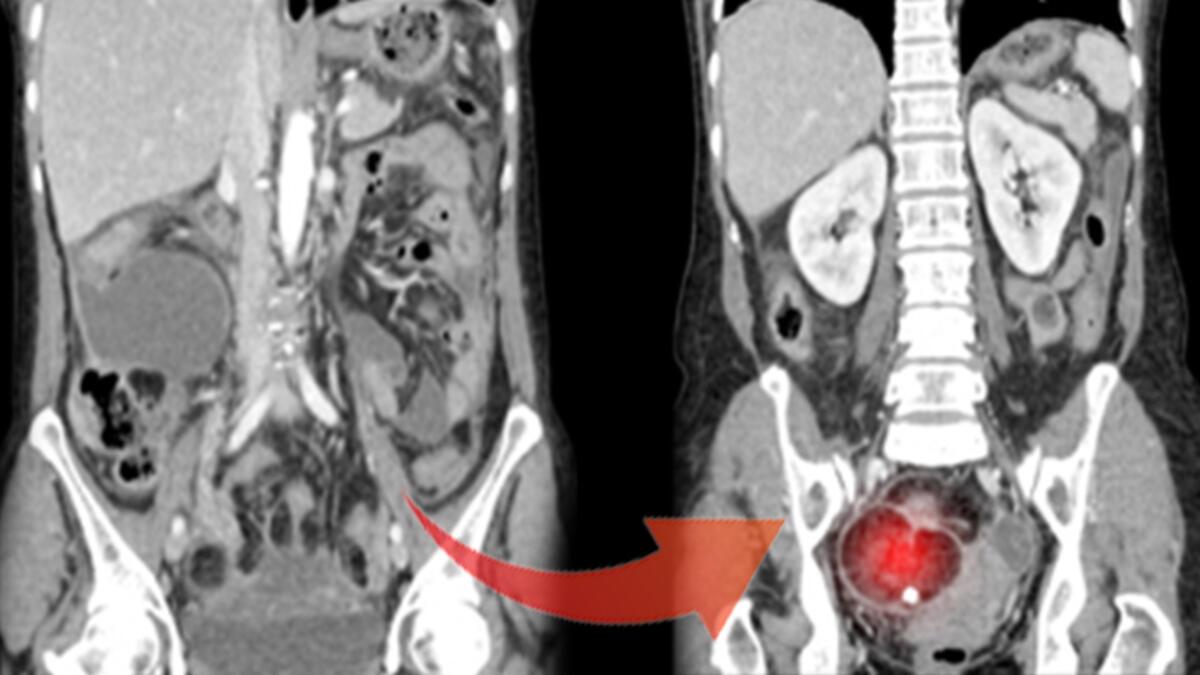

Bir yumurtalık tümöründe diş, kemik, kıl, deri modülleri üzere öbür dokuların varlığının ender bir durum olmadığını söz eden Şimşek, “Bu durum bize tümörün ‘dermoid tümör’ ya da öteki ismiyle ‘matür kistik teratom’ olduğunu gösterir ki genç bayanlarda en sık görülen over tümörü çeşitlerinden biridir” dedi.

Form 1-Dermoid kistli yumurtalık Biçim 2-Normal yumurtalık